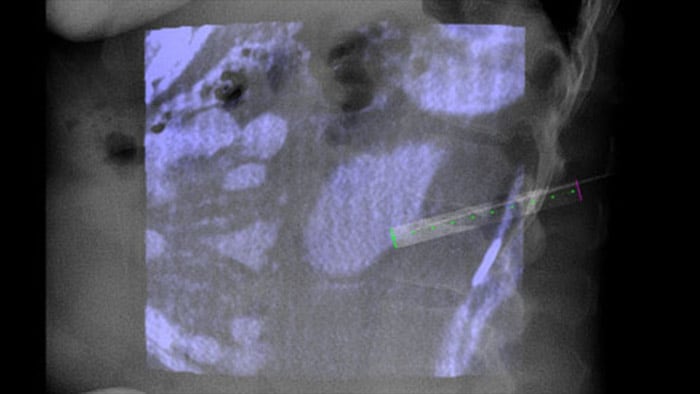

XperGuide biedt zeer nauwkeurige live beeldgeleiding van elke naald naar een doelpositie door overlay van vooraf geplande trajecten met fluoroscopische beeldvorming.3

XperGuide Ablation* biedt uitgebreide hulp bij het plannen van behandelingen en live naaldgeleiding. Het biedt unieke Parallax-correctie om naaldtrajecten te plannen voor laesies die niet in het midden liggen.1 Voor het optimaliseren van de naaldpositie voor effectieve ablatie geeft dit hulpmiddel het virtuele naaldtraject weer om te helpen bij het plannen van meerdere naalden. Het toont naaldkenmerken zoals ablatiezone/isotherm om volledige tumordekking te bevestigen voorafgaand aan ablatie.